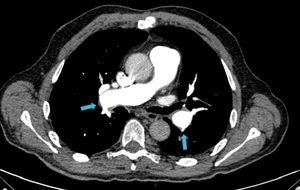

Presentamos el caso de un varón de 58 años diagnosticado de hipertensión pulmonar tromboembólica crónica (HPTEC), sometido a cirugía de endarterectomía pulmonar (EAP) bilateral, con excelente resultado. El paciente, con antecedente de hipertensión arterial bien controlada, con tratamiento con antagonistas de los receptores de la angiotensina II, consultó por astenia y disnea de varios meses de evolución, que había ido en aumento hasta hacerse de mínimos esfuerzos, presentando 7 días antes de su ingreso un episodio de mareo intenso. Su estado general era bueno, con adecuada perfusión de la piel y las mucosas. En la exploración física, la tensión arterial era de 120/64mmHg, la frecuencia cardiaca de 65lpm y la respiratoria de 14rpm. Presentaba ventilación pulmonar conservada y un soplo sistólico en foco tricuspídeo, grado II/IV, sin irradiación y con segundo tono normal en la auscultación cardiaca. La radiografía de tórax mostró una silueta cardiomediastínica dentro de la normalidad, y sin datos de enfermedad pleuropulmonar. En el electrocardiograma se advertía un ritmo sinusal con extrasístoles auriculares aisladas. La saturación arterial de oxígeno (SpaO2) era del 94,2%, con una presión parcial de O2 de 68,0mmHg y una presión parcial de CO2 de 34,0mmHg. La determinación del dímero D resultó normal. La angio-tomografía computarizada (angio-TC) torácica evidenció defectos de repleción en ambas arterias pulmonares principales, compatible con trombo crónico (fig. 1). La eco-Doppler de miembros inferiores no mostró datos de trombosis venosa profunda. Se practicó un ecocardiograma Doppler que mostró un ventrículo izquierdo con diámetros normales con función global conservada, así como una insuficiencia tricuspídea (IT) moderada y una presión sistólica pulmonar estimada (PSAPe) de 125mmHg, con moderada dilatación de cavidades derechas. El paciente fue diagnosticado de hipertensión pulmonar (HP) secundaria a embolia pulmonar (EP) crónica y tratada con anticoagulación. En el seguimiento a los 3 meses, el paciente mantenía disnea clase III de la World Health Organization (WHO), y en la ecocardiografía Doppler cavidades derechas moderadamente dilatadas con una IT leve y una PSAPe de 75mmHg. El estudio de hipercoagulabilidad resultó normal. El paciente fue sometido al protocolo diagnóstico de HPTEC: se practicó una gammagrafía de perfusión pulmonar que mostró múltiples defectos de perfusión intrapulmonares en segmentos superior e inferior de ambos campos pulmonares, hallazgos compatibles con alta probabilidad de EP; la espirometría mostró una limitación ventilatoria restrictiva de grado moderado; la prueba de marcha de los 6min (PM6M), realizada en aire ambiente, mostró una distancia total recorrida de 400m, SpaO2 basal del 94% y SpaO2 final del 88% (puntuación 7 en la escala Borg); el cateterismo cardiaco derecho confirmó una presión media arterial pulmonar (PmAP) de 47mmHg; y finalmente, se realizó una arteriografía digital pulmonar que mostró defectos de vascularización centrales en ambos pulmones, y una coronariografía que descartó enfermedad arterial coronaria. Previa implantación de un filtro de Greenfield en la vena cava inferior, se practicó al paciente una EAP bilateral mediante esternotomía media, con apoyo de circulación extracorpórea y periodos de parada circulatoria intermitente en hipotermia profunda (fig. 2). No se produjeron complicaciones posoperatorias. En el control a los 90 días, tras la cirugía, el paciente se encontraba en clase funcional I de la WHO con una SpaO2 del 99%, respirando aire ambiente. La nueva PM6M mostró una distancia total recorrida de 470m y una SpaO2 basal del 99% con una SpaO2 final del 94% (puntuación 1 en la escala de Borg). El estudio de la función pulmonar resultó normal y el ecocardiograma Doppler mostró una PSAPe de 35mmHg, con cavidades derechas de tamaño normal. En la angio-TC torácica no se identificaron defectos de repleción intravasculares (fig. 3). Todos los pacientes con HPTEC deben recibir anticoagulación indefinida con el fin de prevenir la trombosis in situ y el tromboembolismo recurrente1. La cirugía de EAP es el tratamiento de elección de la HPTEC, en los casos en que se estime que esta intervención permitirá la extracción de una cantidad significativa de material fibrotrombótico de las arterias pulmonares. La EAP es el único tratamiento que puede lograr la curación de la HPTEC, y es apropiada para más del 60% de los pacientes. La EAP consiste en la extracción quirúrgica del material trombótico intravascular organizado, la capa íntima engrosada, a la cual aquel está firmemente adherido, y parte de la capa muscular. La endarterectomía debe ser bilateral y completa, es decir, extirpando el material fibrotrombótico más periférico. Para ello se requiere esternotomía media, circulación extracorpórea y pausas de parada circulatoria completa que permitan visualizar adecuadamente el árbol vascular. Para evitar el posible daño cerebral durante la parada circulatoria, estas se limitan a una duración menor de 20min por lado, y se realizan en hipotermia profunda de entre 18-20°C. La intervención proporciona unos excelentes resultados, con un porcentaje de curación de la HP (valor de PmAP posoperatorio<25mmHg) cercano al 50%, mejoría de la hemodinámica y de la tolerancia al esfuerzo francas, y buena supervivencia a largo plazo2. La EAP no está exenta de complicaciones y requiere de experiencia, tanto del procedimiento quirúrgico como del manejo perioperatorio. La mortalidad en el periodo posoperatorio en los centros con mayor experiencia es actualmente del 4-5%. En un registro en el que se incluyeron 386 pacientes de 26 centros expertos europeos y uno canadiense, la mortalidad en el posoperatorio inmediato fue del 4,7%. Las complicaciones posoperatorias más frecuentes son el edema de reperfusión y la HP persistente tras la cirugía. La decisión debe ser individualizada para cada paciente, puesto que en el éxito de la cirugía interviene la relación que existe entre las lesiones trombóticas accesibles quirúrgicamente y el estado hemodinámico, la función del ventrículo derecho, la edad del paciente y las comorbilidades, entre otros factores. La angioplastia con balón de las arterias pulmonares es una técnica que se ha postulado en los últimos años, y que se podría tener en cuenta para pacientes que se consideran inoperables debido a enfermedad predominantemente distal o a enfermedades asociadas o en aquellos pacientes con HP persistente o recurrente después de la EAP.